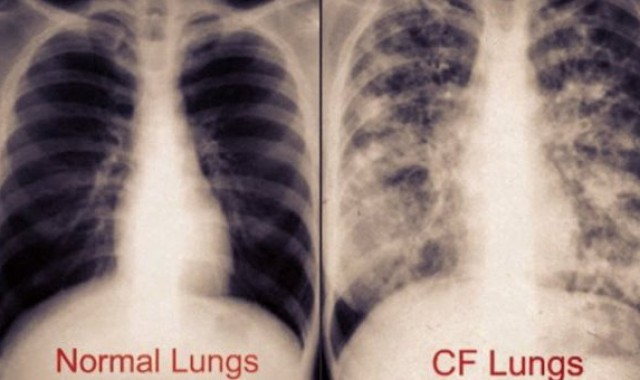

Η Ιδιοπαθής Πνευμονική Ίνωση (IPF) είναι μία χρόνια, μη αναστρέψιμη, προοδευτικά εξελισσόμενη και τελικά θανατηφόρος ινωτική πνευμονική νόσος άγνωστης αιτιολογίας, με διάμεση επιβίωση που εκτιμάται στα 3-5 έτη μετά τη διάγνωση.

Είναι η πιο συχνή από τις ιδιοπαθείς διάμεσες πνευμονίες και περιορίζεται μόνο στους πνεύμονες. Οι περισσότεροι ασθενείς αρχικά παρουσιάζουν δύσπνοια στην κόπωση και ξηρό βήχα. Η δύσπνοια προοδευτικά επιδεινώνεται και στα προχωρημένα στάδια της νόσου οι ασθενείς δυσκολεύονται πολύ να αναπνεύσουν. Η νόσος μπορεί να εξελιχθεί με ταχύ ή βραδύ ρυθμό, αλλά τελικά οι πνεύμονες θα ουλοποιηθούν και θα σταματήσουν να λειτουργούν αποτελεσματικά (αναπνευστική ανεπάρκεια). Η IPF εμφανίζει χειρότερη επιβίωση από τους περισσότερους καρκίνους. Σε μία πρόσφατη μελέτη, μόνο ασθενείς με καρκίνο των πνευμόνων και του παγκρέατος φάνηκε να έχουν χειρότερη επιβίωση.